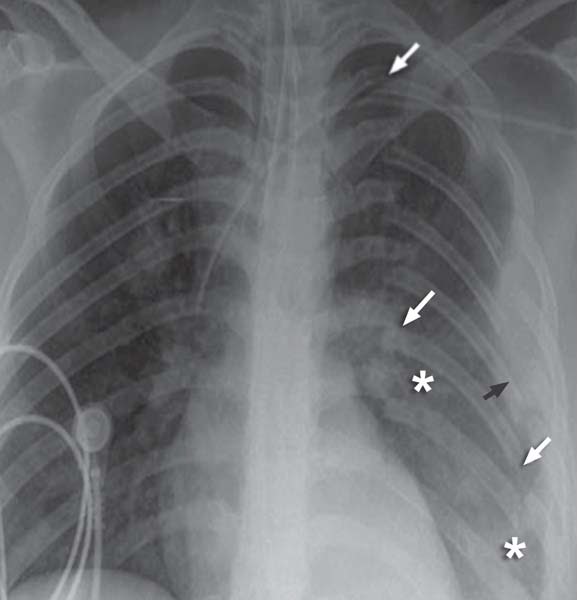

to LearningRadiology flail, chest, trauma, rib, fracture What Does A Flail Chest Look Like Flail chest is when three or more adjacent ribs are fractured in at least two places, causing paradoxical motions in the chest. When three or more ribs. Flail chest is a particular kind of rib fracture that is defined as three (or more) ribs that are broken in two (or more) places. Flail chest is an injury that occurs typically. What Does A Flail Chest Look Like.

Chest Xray showing a flail chest of the right haemithorax with two What Does A Flail Chest Look Like When three or more ribs. Flail chest happens when multiple adjacent ribs are broken in multiple places, creating a segment of the chest wall that moves independently. Flail chest is when three or more adjacent ribs are fractured in at least two places, causing paradoxical motions in the chest. Flail chest is a particular kind of rib fracture that is. What Does A Flail Chest Look Like.